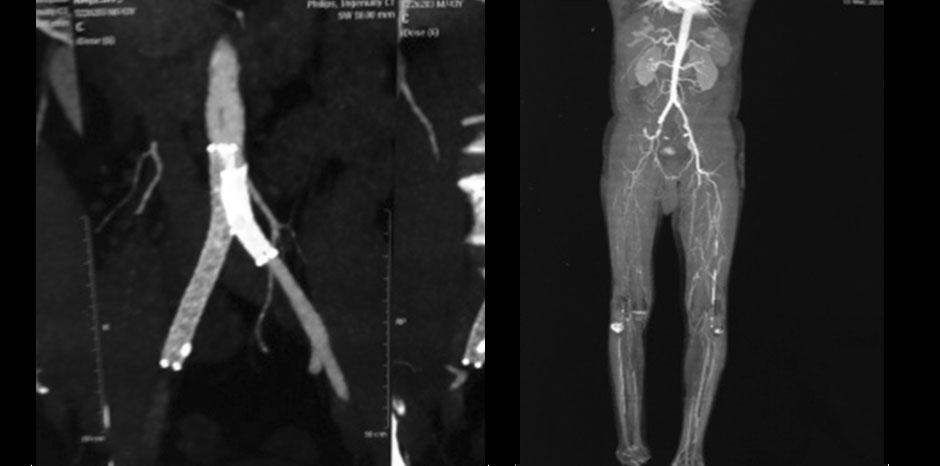

• Angiography : B/L Iliac artery stenosis ( R-80%, L-50%) with B/L SFA occlusion distal to adductor canal extending onto popliteal artery

• B/l Iliac artery stenting with left femoro-popliteal bypass done in March 2013

• Now presented with rest pain and non healing ulcer over right leg amputation stump since Jan 2014

RIGHT GROIN EMBOLECTOMY sos RIGHT ILIAC STENTING